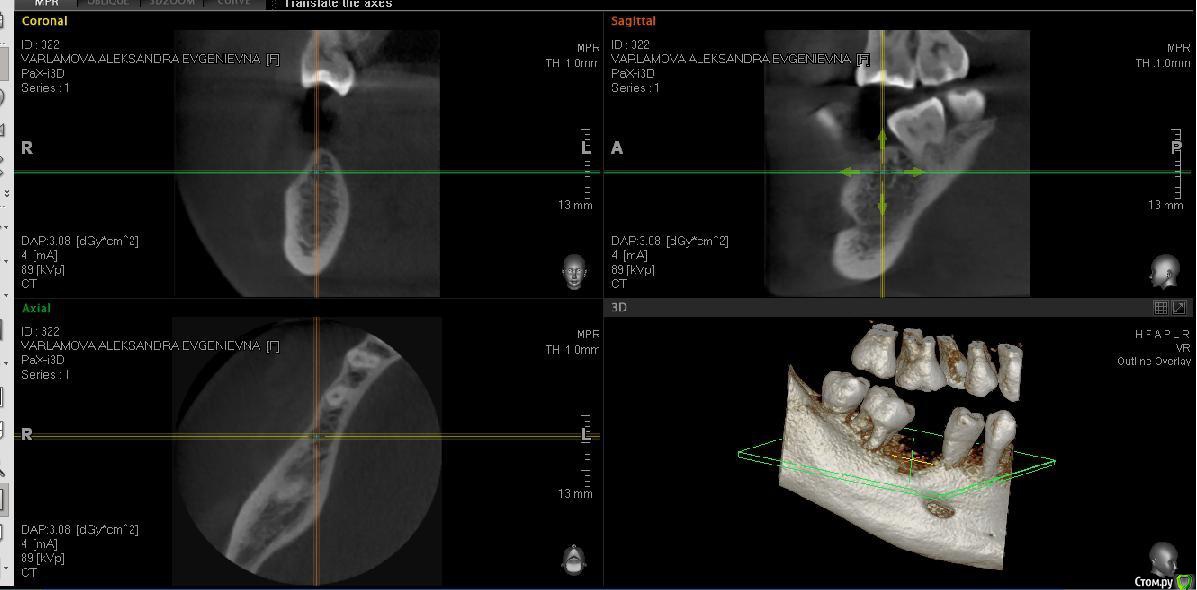

Александра_85 Опубликовано 12 марта, 2015 Поделиться Опубликовано 12 марта, 2015 (изменено) Здравствуйте, собираюсь сделать имплантацию 6 нижнего зуба справа.Удален этот зуб был 4 года назад, кость довольно сильно ушла.Мой имплантолог советует кость не наращивать, и установить тонкий импрант АльфаБио.Хотелось бы услышать ваше мнение.Во вложении ортопантограмма годичной давности, и свежее КТ по ссылкеhttp://www.fayloobmennik.net/4686662 Я не очень понимаю, как выложить срез.Сделала скрин, может по нему будет понятно Изменено 12 марта, 2015 пользователем Александра_85 Ссылка на комментарий

Александра_85 Опубликовано 12 марта, 2015 Автор Поделиться Опубликовано 12 марта, 2015 да, пожалуйста, ждем снимокВот. Ссылка на комментарий

red_butler Опубликовано 12 марта, 2015 Поделиться Опубликовано 12 марта, 2015 (изменено) Вот.я бы имплантировал с одномоментной костной пластикой, однако существует современная тенденция - ставить импланты малого диаметра и ограничиваться пластикой десны Изменено 12 марта, 2015 пользователем red_butler 1 Ссылка на комментарий